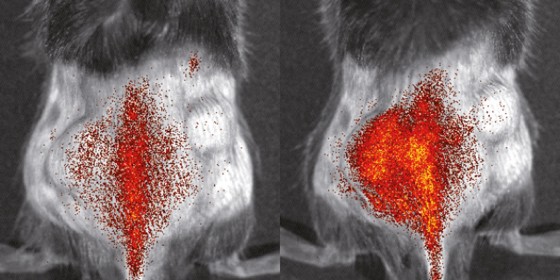

Distribution of immune cells in the body of a mouse, imaged with optical imaging<address>© S. Gran & L. Honold et al./Theranostics 2018(8)</address>

Distribution of immune cells in the body of a mouse, imaged with optical imaging

© S. Gran & L. Honold et al./Theranostics 2018(8)

They have been working for years on techniques that enable them to visualize the dynamics and interactions of immune cells in living organisms in the best possible way. For this purpose, the scientists and their international colleagues use for example positron emission tomography and optical imaging. A major goal of the new project is to develop suitable methods for monitoring immune cells before, during and after immune treatment. The researchers will initially look at the processes in animal models for different diseases – with the aim of translating the results and methods to patients mid-term enabling them to establish image-guided immunotherapies with improved efficacy in diseases such as cancer or inflammation.